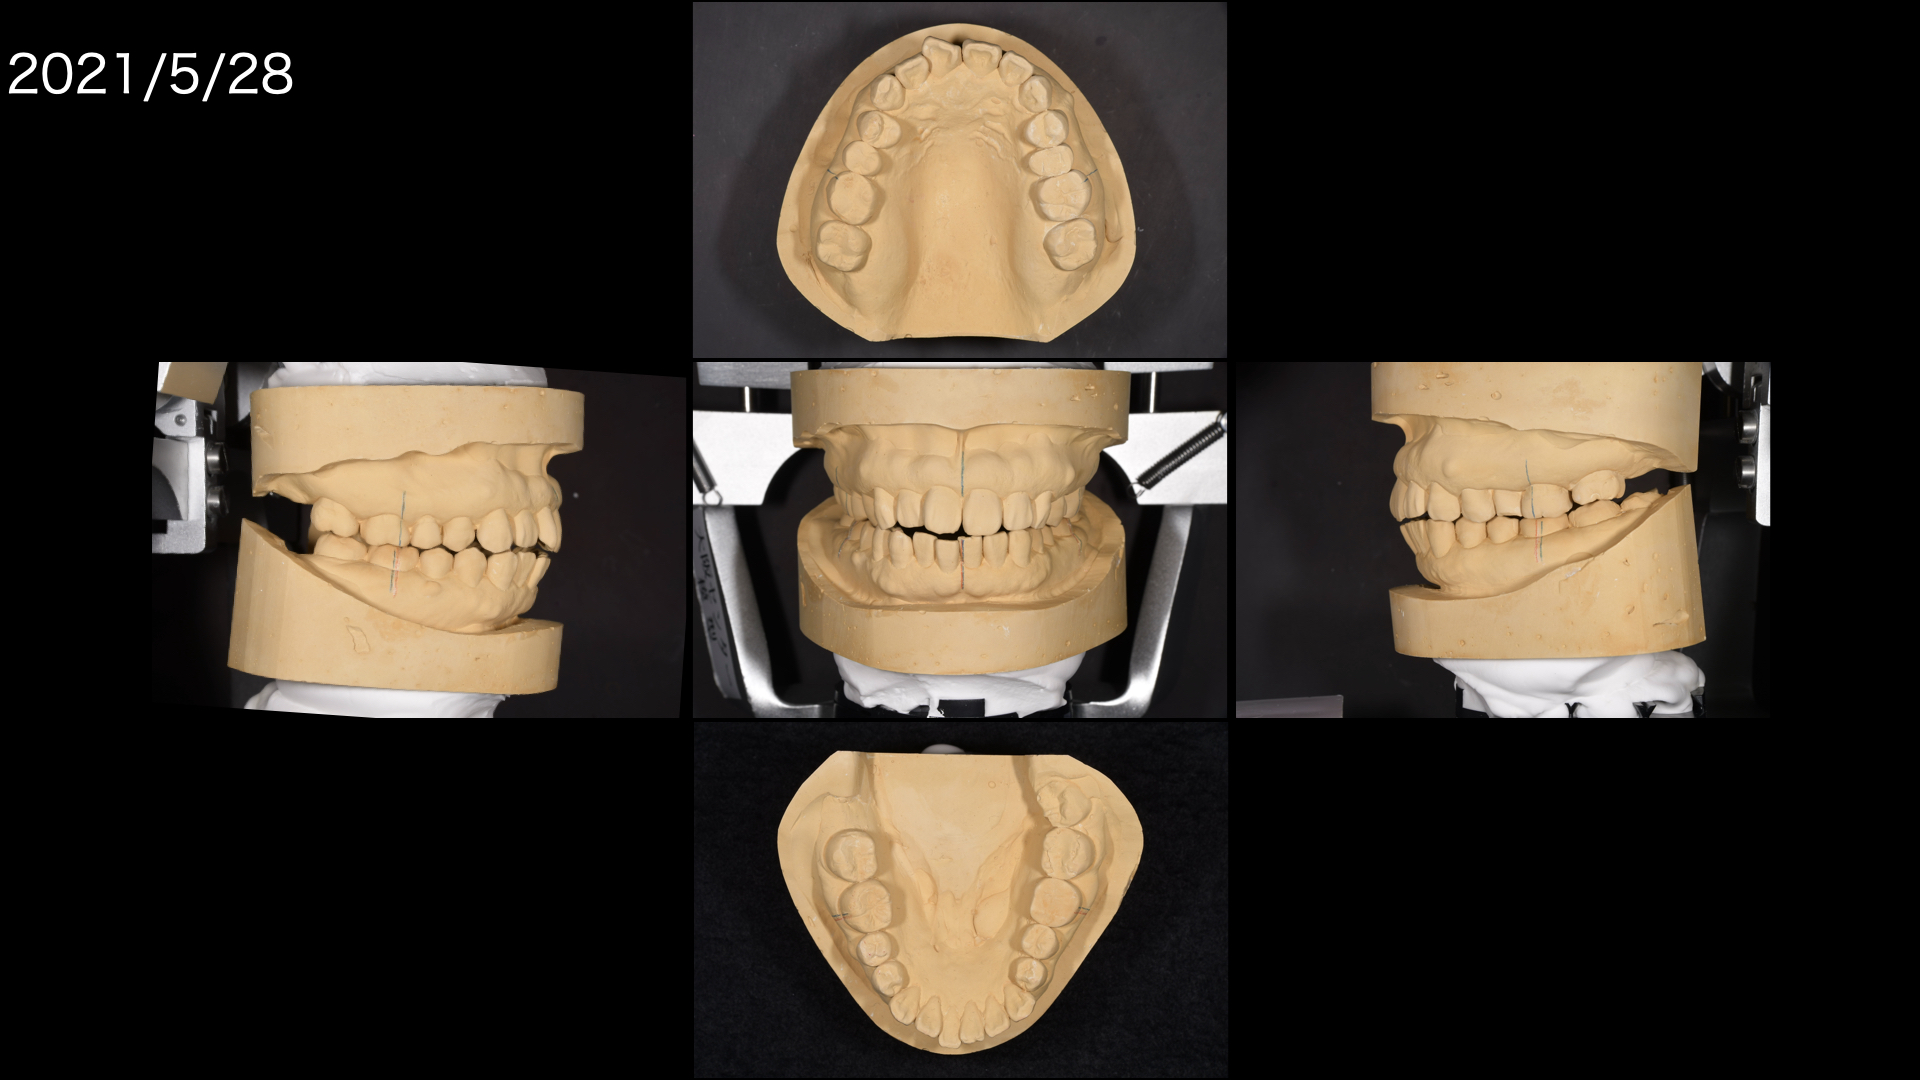

矯正の診断をおこないました。

そこで矯正をせずに前歯を噛ませるにはどうしたらよいか。模型上でシミュレーションをしました。

すると、茶色のwaxの部分は足しているところで、鉛筆の斜線は削っているところです。

下の前歯はほとんど足す必要があり、多くの歯を治療しなければいけません。

どうしても全体的な矯正治療(平均2〜3年)を望まれなかったので、模型上で咬合調整をおこない、やや前歯が噛み合うところまで調整すると矯正治療期間が短くなります。

模型上で、そこから歯を並べて(排列)みて奥歯をさわらずに短い期間で矯正治療ができるのかをシミュレーションした結果

可能ということがわかったので、この計画にしました。